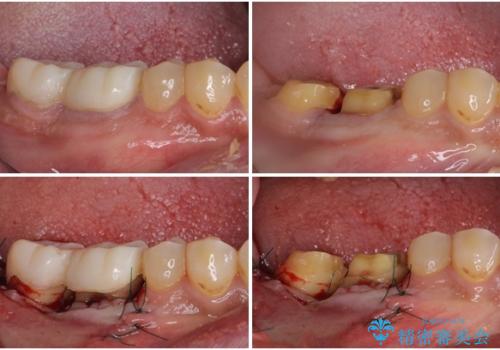

親知らずは速やかに抜歯し、手前の歯とその前の歯に歯槽骨にまで及んだ虫歯が認められたため、歯槽骨を削るなどの歯周外科処置を行うこととしました。

外科処置後の経過を待って、フルジルコニアクラウンにて補綴することとしました。

通っていた歯科医院では、抜歯の可能性が高いと言われていたようですが、何とか健全な状態で歯を保存することができました。

歯周外科処置は、術後に痛みを感じたり、歯肉の状態が落ち着くまで歯がしみたりと苦痛を伴いますが、適用となる場合には抜歯を回避する手段として大変有効です。